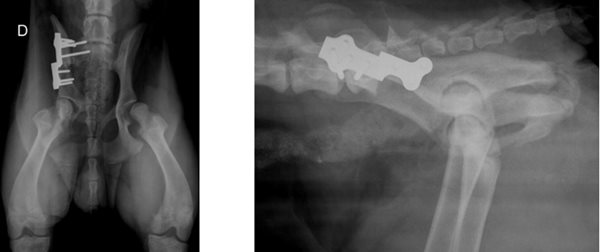

The principle of the operation is to make three cuts on the pelvic bone (triple osteotomy) to mobilise the acetabulum and tip it forward. This tilting effect increases the femoral head's dorsal overlap through the acetabulum and stabilizes the hip by neutralizing subluxation.

- The iliotomy: by the lateral approach of the ilium, a transversal section of the ilium is created which allows the acetabulum to be freed and tilted ventrally. This osteotomy is stabilized by a preformed osteosynthesis plate for triple pelvic osteotomy which allows giving exactly the desired angle of rotation.